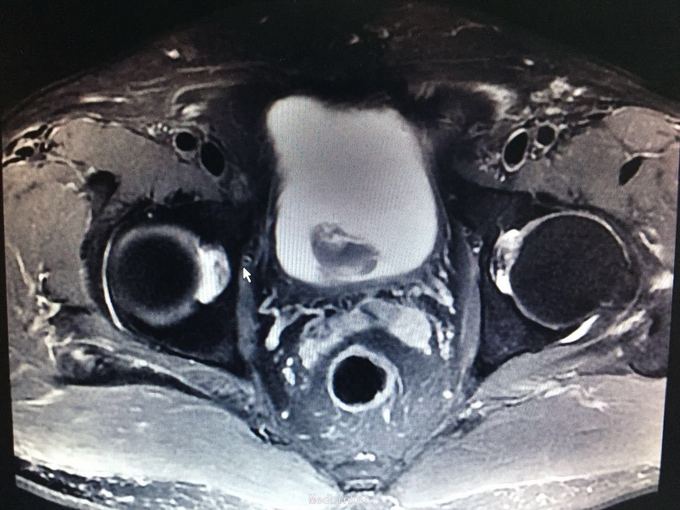

肉眼血尿一周余。 患者一周前无明显诱因出现肉眼血尿。遂于我院就诊,门诊膀胱镜提示:膀胱左侧巨大占位,未窥及基底部。今为进一步治疗收入我科。 九年前于上海行膀胱部分切除术。 81岁,男性患者

查体:无殊。 门诊MRI提示膀胱多发肿瘤,累及深肌层。

高龄患者,既往膀胱部分切除术后,拟行全膀胱切除术。